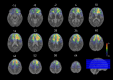

Figures